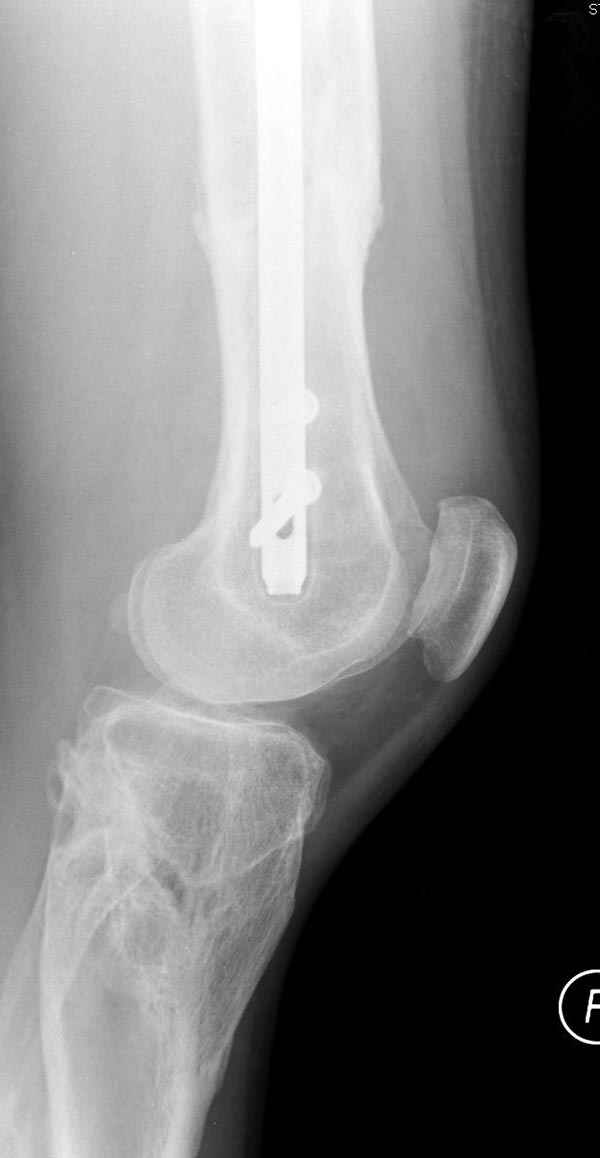

Инфекция канала и стрессовый перелом:

Представляю снимки больного с политравмой: леченного в другом мед.учреждении по поводу открытого перелома бедра, сперва аппаратом наружной фиксации, затем пластиной. Обратился к нам через 8 месяцев после удаления пластины с проблемой несросщего перелома бедренной кости, без клинических проявлении к инфицированию (не все снимки сохранены)

Рутинный интрамедуллярный остеосинтез с расверливанием и с фиксацией реконструктивным трокантерик штифтом (рис №1, №2),

если первые 4 месяца послеоперационного периода проходил без проблем, но на 5 месяце появились боли в дистальном отделе бедра и температура, т.е. симптомы медуллярного инфицирования (рис №3, №4).